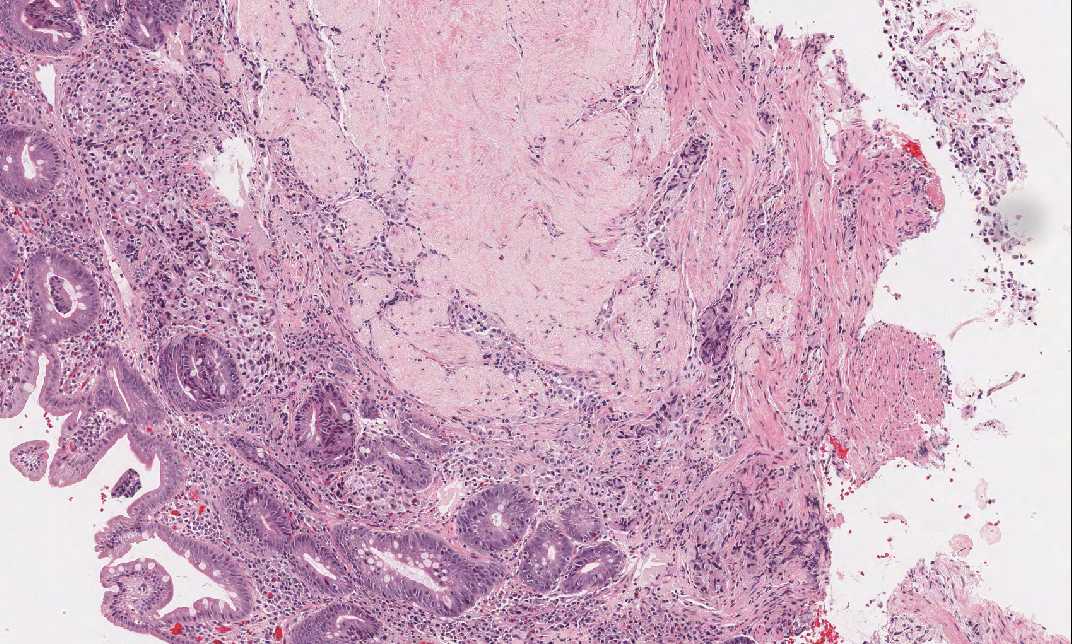

Area 2: This is the area of residual gastric mucosa with chronic atrophic gastritis and intestinal metaplasia.

Area 3: The overall feature of the tumor is that of a cellular neoplastic epithelial proliferation with a myxomatous stroma and no distinct glandular formation. The overall arrangement of the tumor cells and the nuclear features suggest an neuroendocrine carcinoma.

Area 4: The tumor invades into the muscularis propria.

• The tumor (Area 2) is composed of a cellular, neoplastic, epithelial proliferation with rather monotonous cells and monotonous nuclei. There is a myxomatous backgound. On medium magnification, one can appreciate the trabecular or organoid arrangement of tumor cells that are frequently seen in well differentiated neuroendocrine carcinoma (carcinoid). The tumor invades into the muscularis propria (Area 3).